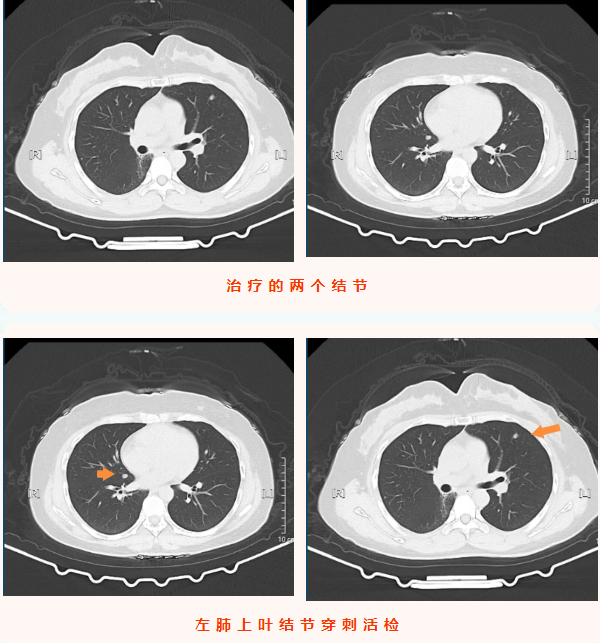

2025年11月24日,王女士的复查影像学检查显示:左肺上叶上舌段可见一大小仅0.8cm×0.5cm的微小实性结节,右肺斜裂处可见0.7cm×0.6cm的实性结节,均为较前新增病灶。结合患者六年前气管腺样囊性癌病史,高度怀疑为转移瘤。由于病灶性质不明且存在转移可能,王女士为求进一步精准诊疗来到宝鸡市人民医院胸心肿瘤外科,门诊以“左肺上叶继发恶性肿瘤”将其收入院。值得注意的是,患者此次就诊全程无咳嗽咳痰、发热寒战、胸闷气短等任何典型症状,完全是通过规律复查发现的早期病灶,为后续干预赢得了有利时机。

入院后,医疗团队结合患者既往腺样囊性癌病史、影像学检查结果,术前综合评估后高度怀疑双侧肺结节为肿瘤转移灶。考虑到患者无明显症状、病灶相对局限,为最大限度减少患者创伤、避免二次手术,团队决定为其同期实施双侧肺结节诊疗手术——即CT引导下经皮左肺上叶微小结节穿刺活检+微波消融术,同期对右肺结节行微波消融术。手术由科主任陈瑜主刀,副主任吴明君担任助手,魏宝、张宝军为第二助手。手术过程中,医师团队首先聚焦左肺上叶仅0.8cm×0.5cm的微小实性结节,在左侧腋下及前外侧胸壁精准标记,在患者平静呼吸状态下通过CT反复扫描确认穿刺参数,成功获取活检组织。并按计划对左肺穿刺后的结节及右肺斜裂结节同期实施微波消融术,精准破坏双侧病灶组织。整个手术过程一气呵成,同期完成双侧病灶诊疗,术中患者生命体征始终平稳。

术后,患者安返病房,生命体征稳定,无胸痛、咯血、气胸等不适症状,饮食睡眠恢复良好。术后病理结果回报,明确左肺上叶结节为腺样囊性癌转移灶,与术前评估判断一致,为后续诊疗方案制定提供了金标准依据。本例患者无任何症状,正是通过定期复查实现转移病灶的早期发现;同时彰显了“诊断+治疗”一体化微创技术的临床价值,为恶性肿瘤转移灶的早期干预提供了高效、精准的诊疗范式,有力保障了肿瘤患者的长期生存质量。(来源:宝鸡市人民医院)